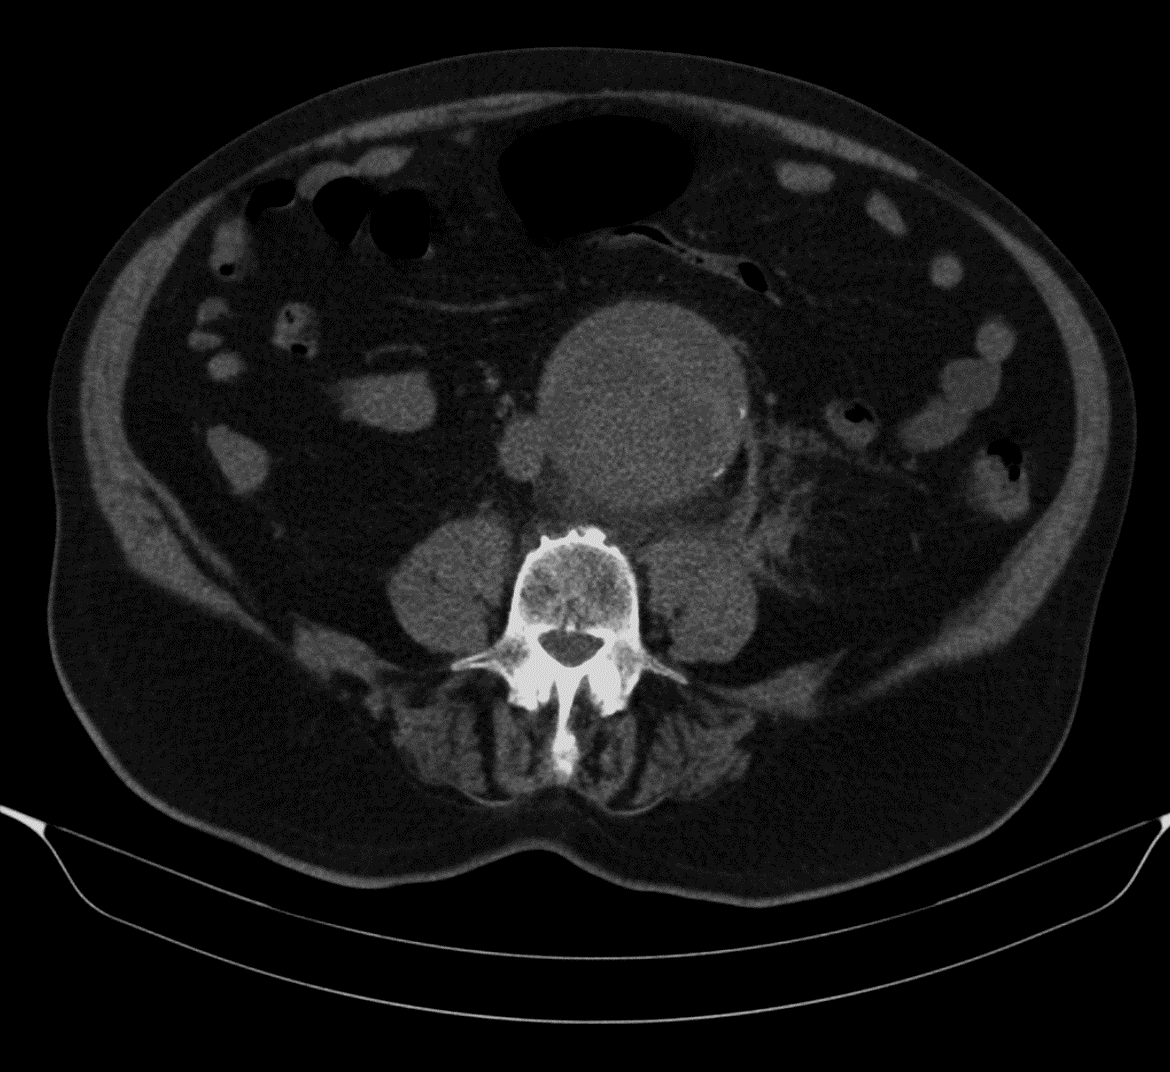

En caso de no haber hallazgos claros de patología abdominal que expliquen el dolor en la primera prueba realizada, que normalmente será una ecografía, se debe realizar una TC. Esta es la estrategia que más sensibilidad tiene, con menor dosis de radiación acumulada en el paciente [1]. Además, la TC es la prueba que más sensibilidad tiene en el abdomen [1]

En este caso se realiza una TC y no una ecografía porque la primera prueba de imagen ha dado hallazgos sugestivos de la patología que tiene el paciente y que causa el dolor. Como la TC es el paso lógico a dar en esta patología y la ecografía no aportará información añadida, no se pierde tiempo con ella.